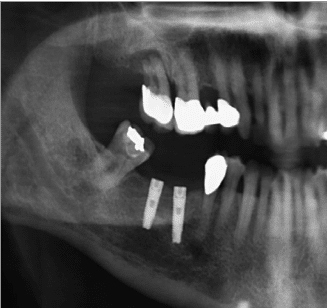

Cette technique sûre et efficace s’appuie sur des données scientifiques avec un recul clinique de plus de 20 ans. La pose d’un implant, réalisée sous anesthésie locale, est totalement indolore. Elle se pratique au cabinet dentaire ou en clinique. Le choix se fait en fonction de l’emplacement, de la quantité d’os disponible, et des éléments anatomiques environnants à partir d’un examen radiologique et scanner de la zone à implanter.

Le chirurgien-dentiste après une anesthésie locale pratique une incision, puis il décolle la gencive pour accéder à l’os alvéolaire. Ensuite il prépare l’emplacement de l’implant dans l’os en passant plusieurs forêts de diamètre croissant.

Le forage de l’os se fait à vitesse maitrisée et lente sous irrigation, pour respecter la structure et éviter tout échauffement de l’os. Le praticien arrête lorsqu’il à obtenu un puit d’un diamètre très légèrement inférieur à l’implant à poser.

L’implant est placé dans l’os le plus souvent par vissage et doit avoir une forte stabilité dans l’os.